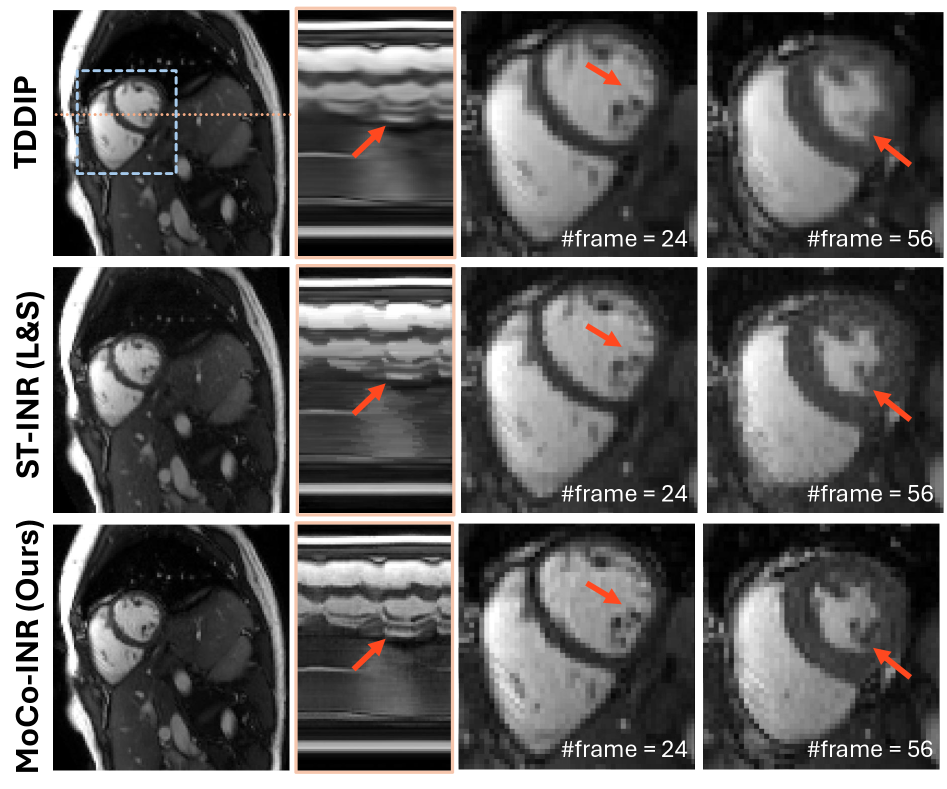

Refer to caption

Figure 4: Qualitative results of prospective reconstruction under free-breathing scans.

We further evaluate the proposed MoCo-INR and the compared methods on prospectively undersampled data. The visual comparison is illustrated in Fig. 4, consistent with the observations from the retrospective study. TDDIP exhibits over-smoothing in both spatial and temporal dimensions, and the zoom-in views reveal anatomically implausible structures. Compared with ST-INR (L&S), the proposed MoCo-INR yields sharper tissue detail with significantly reduced artifacts, as highlighted by the red arrows. Notably, the intensity profile shows that, although ST-INR (L&S) suffers from spatial noise, it fails to capture temporal detail, whereas MoCo-INR successfully resolves both large-scale cardiac motion and subtle intramural deformations.